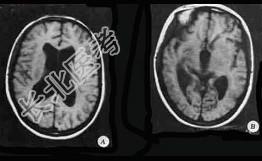

- 单项选择题如图所示,可以得出 ( )

A、导水管轻度扩张,四脑室轻度增大

B、中脑导水管狭窄

C、侧脑室及第三脑室扩大

D、颅内血肿